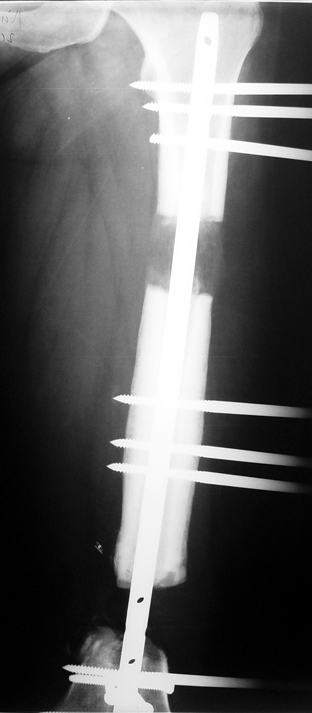

Vaka 1